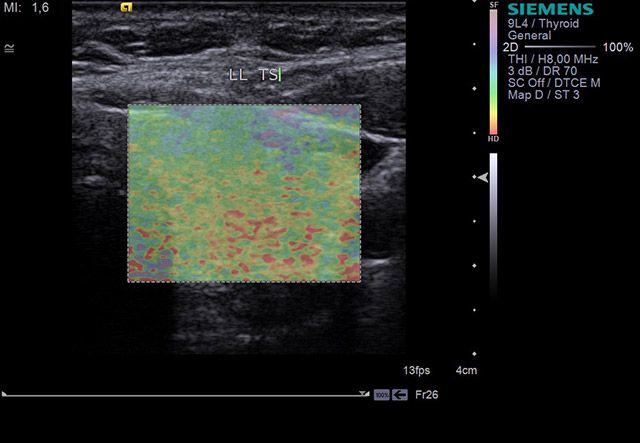

ΕΛΑΣΤΟΓΡΑΦΙΑ

SHEAR WAVE & STRAIN

Η ελαστογραφία μαστού είναι μια νέα και πολλά υποσχόμενη απεικονιστική μέθοδος που επιτρέπει στους επιστήμονες να διαγνώσουν τα καλοήθη ογκίδια, ξεχωρίζοντας τα από τους κακοήθεις όγκους αλλά και τις ύποπτες για κακοήθεια αλλοιώσεις στο μαστό.

Είναι ουσιαστικά μια νέα τεχνική στους υπέρηχους, που ασκεί μια μικρή πίεση στους εντοπισμένους όγκους, μετρώντας την ελαστικότητά τους. Ο καρκίνος γενικά εμφανίζει μεγαλύτερη σκληρότητα, επομένως η ελαστογραφία μπορεί να δώσει τις αναγκαίες πληροφορίες έτσι ώστε να μειώσει τις βιοψίες μαστών μόνο στις απόλυτα απαραίτητες.

Γίνεται δυνατή η υποκατάσταση της βιοψίας με βελόνα, ιδιαίτερα στα όργανα στα οποία η προσπέλαση με βελόνα είναι τραυματική και δύσκολη. Η υπερηχογραφία και η ελαστογραφία φθάνουν κοντά στην ιστολογική διάγνωση όχι μόνο στα επιφανειακά όργανα (θυρεοειδής, λεμφαδένες, μαστός), αλλά και στα εν τω βάθη όργανα (ήπαρ, πάγκρεας, νεφρός, προστάτης, μήτρα, ωοθήκες).

Η ελαστογραφία είναι μια τεχνική αξιόπιστης μέτρησης της ελαστικότητας και της σκληρότητας των ιστών. Στο πλαίσιο της οικονομικής κρίσης που όλοι ζούμε η υπερηχογραφία έχει ένα κομβικό ρόλο γιατί αντιπροσωπεύει μια από τις τεχνολογίες που μπορούν να αποδίδουν σημαντικό διαγνωστικό όφελος με μικρό κόστος, σε αντίθεση με τις βαρύτερες απεικονιστικές τεχνολογίες, όπως είναι η αξονική τομογραφία και η μαγνητική τομογραφία).